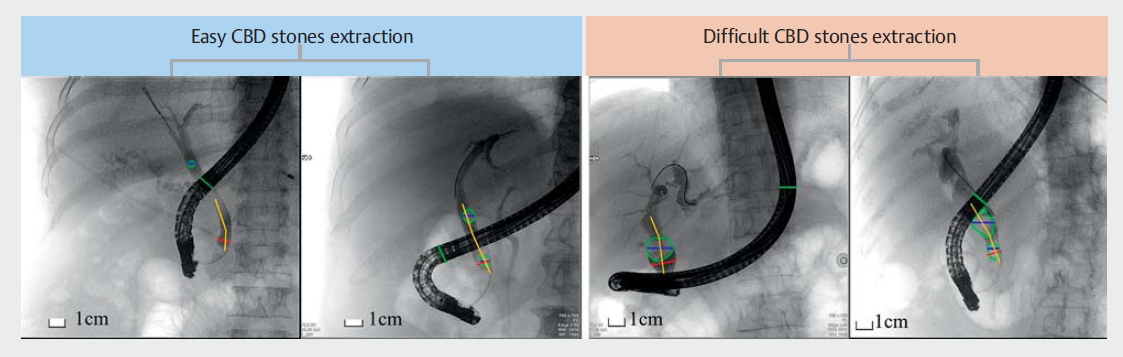

图1. 简单组(a、b)和困难组(c、d)组的典型胆管造影。根据与胆总管(CBD)解剖和结石特征相关的5个因素来评估技术难度。 1.石头的大小-最大的石头的大小。 2.十二指肠镜的直径-胆管造影上的十二指肠镜的范围大小。 3.远端CBD直径-远端CBD被定义为距离大壶腹开口1cm的近端部分。 4.远端CBD角度-沿CBD过程从壶腹孔开始的第一个角度。 5.远端CBD臂-壶腹孔与远端CBD成角的角点之间的长度。

在2020年9月1日至2021年6月15日期间,共从三家医院招募了231名CBD结石患者。其中,173人符合纳入标准。共有58名患者被排除在外,原因如(图3)所示。患者队列的特征如(表1)所示。总共有46名评分为0或1的患者被计算机辅助设计系统归类为困难组,127名评分为2或以上的患者被归类为容易组。图1显示了两组的四个典型图像。